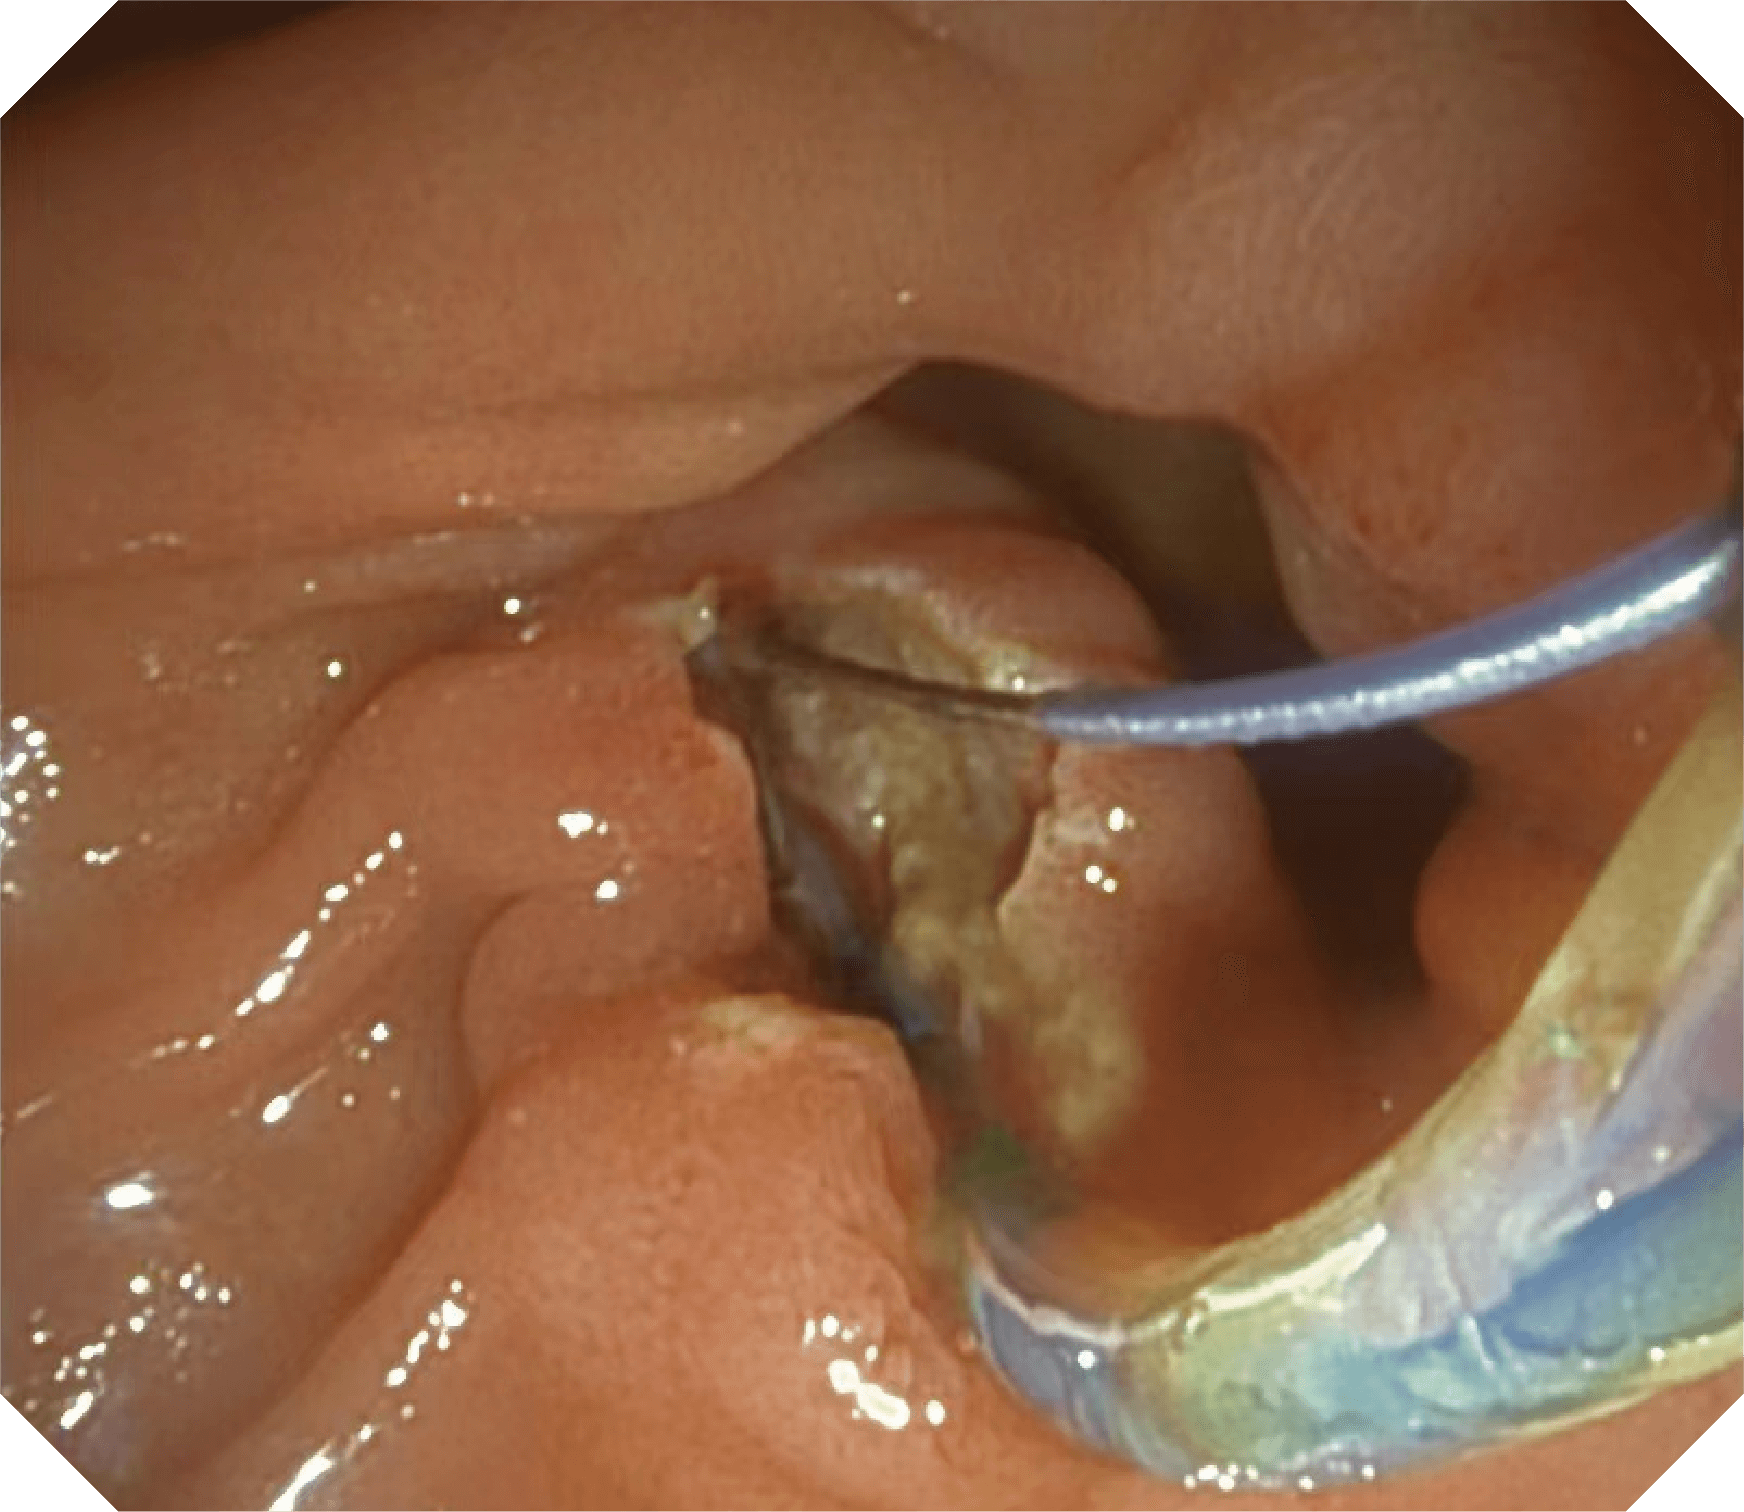

4.2mm大钳道,器械交换更顺畅

优异的手术器械抬举性

更好的通过性,更稳定的镜体支撑力